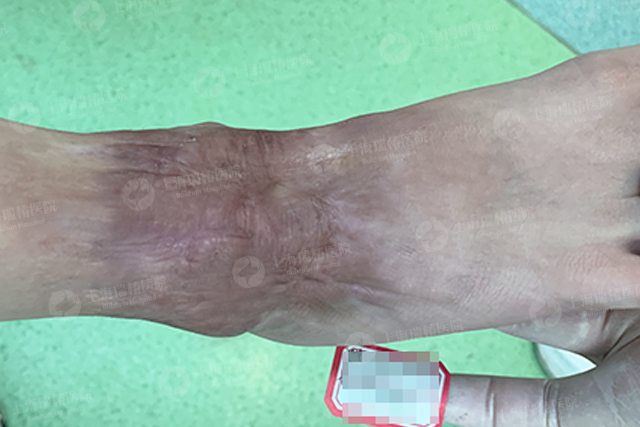

丁诗珂-脚腕-增生性疤痕

增生性疤痕